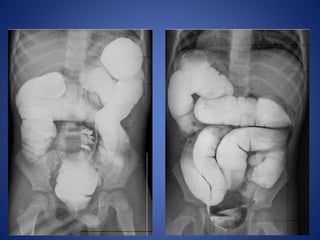

Total Colonic Aganglionosis—Long Segment

Hirschsprung Disease

Hirschsprung disease ---

It can be anatomically divided into 4 types according to the length

of the aganglionic segment:

• short segment disease : ~ 75% *

rectal and distal sigmoid colonic involvement only

• long segment : ~ 15%

typically extends to splenic flexure / transverse colon

• total colonic aganglionosis : 2 - 13%

also known as Zuezler-Wilson syndrome

occasional extension of aganglionosis into small bowel

• ultrashort segment disease

3 - 4 cm of internal anal sphincter only